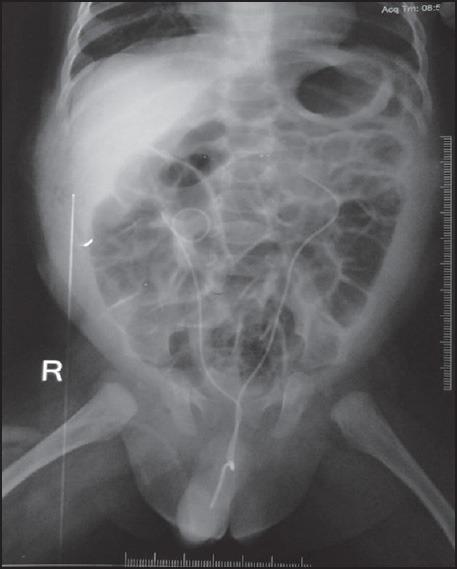

This was a prospective randomized study of 20 patients in each group over 14 months. Pre and post-operative (3 months) function and drainage were assessed by ethylenedicysteine scan and intravenous urogram.

Both groups showed similar good improvement in function and drainage. Nephrostomy group had significantly longer hospital stay (P < 0.001) but incurred less cost. Complications with nephrostomy included tube breakage (n = 1) and urine leak after tube removal (n = 2). DJ stents were associated with stent migration (n = 4), increased frequency of micturition (n = 9), dysuria (n = 4) and urinary tract infection (n = 1).

这是一项前瞻性随机研究,每组20例患者,研究为期14个月。术前及术后3个月通过乙二巯基丁二酸扫描和静脉肾盂造影评估肾功能及引流情况。

两组在功能及引流方面均有相似的良好改善。肾造瘘组住院时间显著更长(P<0.001),但费用更低。肾造瘘的并发症包括造瘘管断裂(1例)及拔管后尿漏(2例)。DJ管相关并发症包括支架移位(4例)、排尿频率增加(9例)、排尿困难(4例)及泌尿系统感染(1例)。